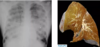

What is emphysema?

Permanent loss of the alveolar parenchyma distal to the terminal bronchiole

What does lung bullous rupture cause?

Pneumothorax

How does diffuse alveolar damage appear on gross histopath?

Fluffy white infiltrates in all lung fields -“whiteout on all lung fields”

Lungs expanded/firm, plum coloured, airless, often weight >1kg